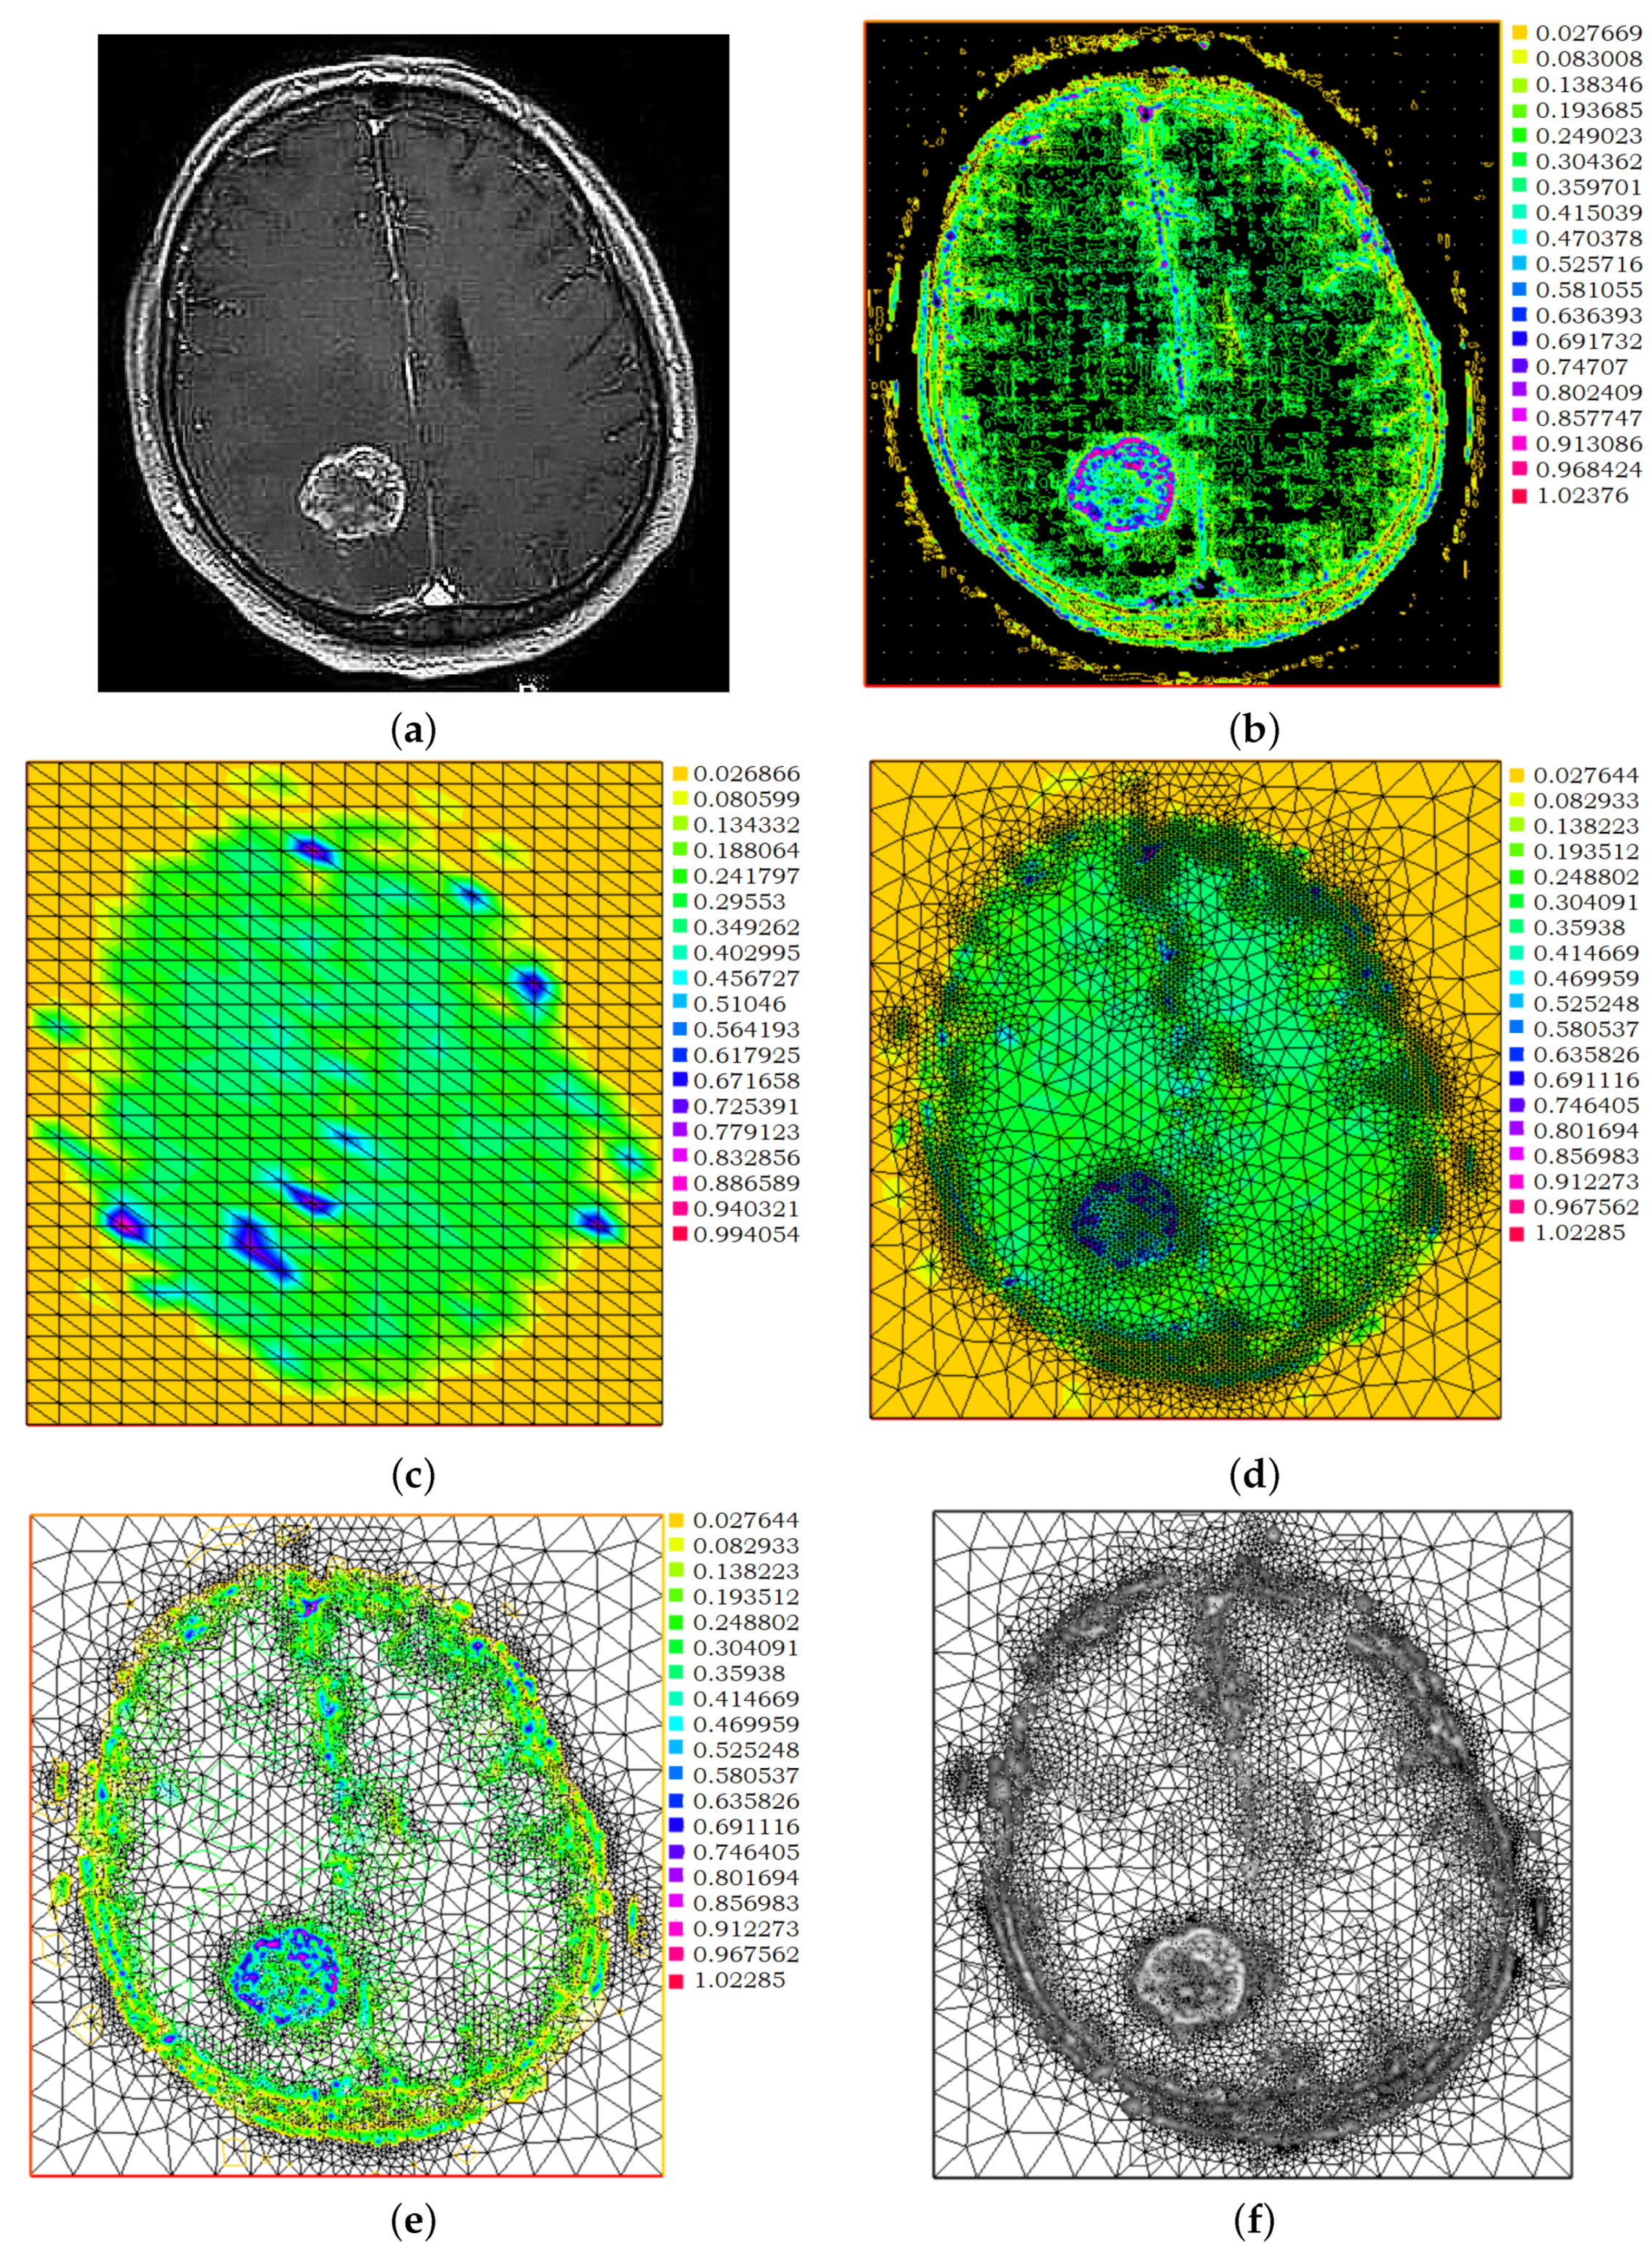

A Metastatic Brain Tumor Example

3.1. Pre-Processing

3.2. Post-Processing